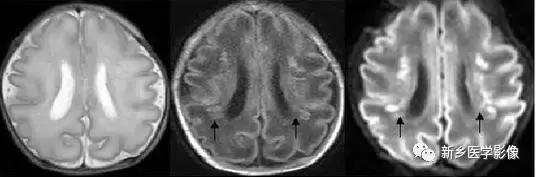

6.脑室周围白质软化症

主要与缺血缺氧及感染有关。

常见于早产儿。常见于早产儿的原因与胚胎期脑部损害发生的时间有关,胚胎早中期脑损害主要引发发育畸形,晚期主要引起脑血管改变。

由于脑室周围白质的血供分别来自脑室区和远脑室区的终动脉,未成熟儿终动脉深穿支的侧支循环尚未建立,而胚胎晚期脑室周围白质对缺血缺氧敏感。所以,脑室周围白质软化症多见于早产儿。

由于侧脑室周围有软化萎缩,故扩大的侧脑室外缘常不规则,不光整,这种不规则、不光整是本病引起脑室扩大的特征,另外,本病均表现有脑白质量减少及脑白质内斑片状软化病灶,脑白质减少严重时表现为部分区域白质消失,脑皮层与脑室侧缘接近甚至相连。CT表现为斑片状低密度灶。MR T1WI上呈低信号,T2WI呈高信号。